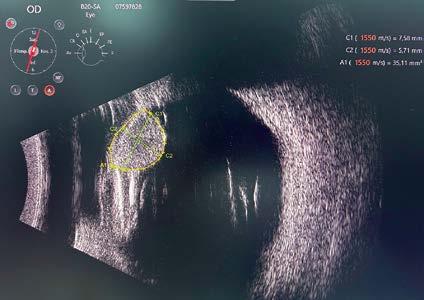

26 ¿Sabe cuál es la prevalencia de quistes en el sulcus ciliar de sus pacientes miopes? Relevancia en implantes fáquicos de cámara posterior

Autor: Dr. Germán R. Bianchi

Sin embargo, hay problemas que pueden evitarse, especialmente en el ámbito de nuestra actividad profesional. Un ejemplo de ello es la presencia de quistes de cuerpo ciliar, cuya existencia puede complicar los resultados en la implantación de lentes intraoculares fáquicos. Tal como explica el doctor Germán Bianchi, estos problemas pueden detectarse y evitarse mediante un examen preoperatorio con UBM.